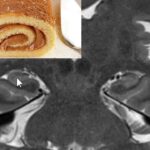

Uma segunda via muito bem estudada são os emaranhados de proteína tau. Quando a proteína tau sofre algumas reações químicas, como por exemplo, a fosforilação, ela se agrega formando emaranhados neurofibrilares tóxicos. Assim, um neurônio tende a morrer.